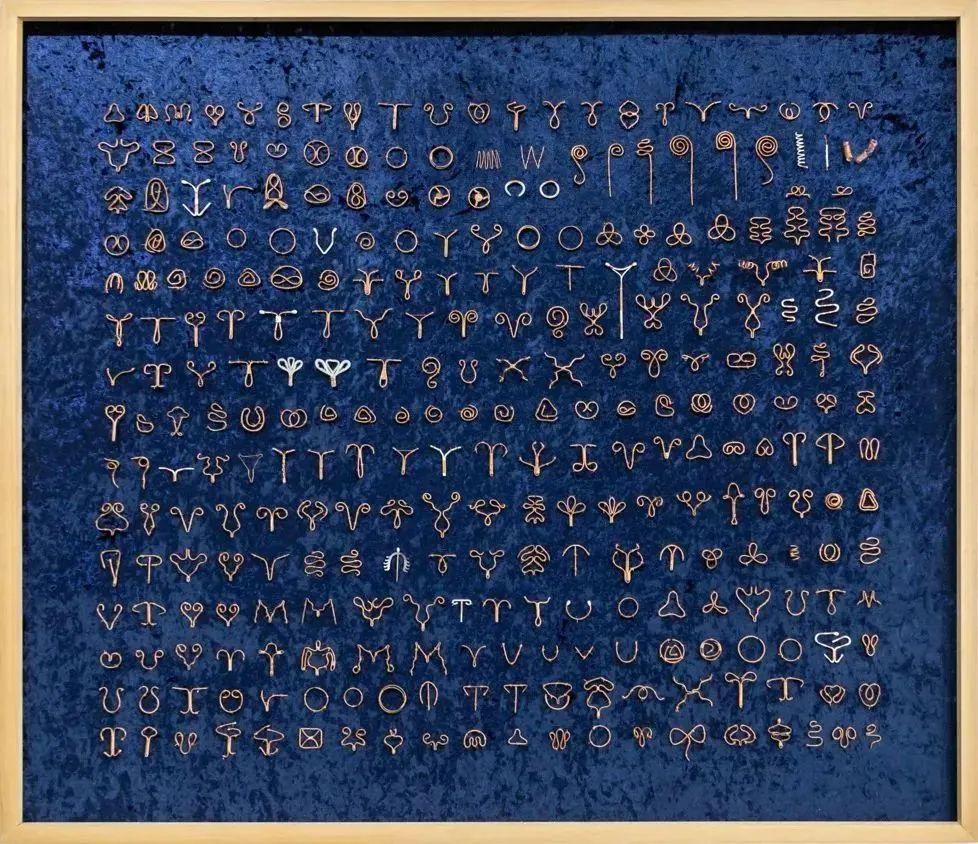

2020年,青年艺术家周雯静制作出了她的第一件当代艺术作品:《女人系列:节育环》。

这是一种曾经被广泛使用的节育工具,它的作用是刺激宫腔内产生炎症反应,干扰受精和着床。长期佩戴,有可能会经血增多、持续少量阴道出血、腰酸背痛。

甚至有人因为节育环不适配而导致子宫增生,最后不得不摘除整个子宫。

蓝色丝绒上,300个人类历史上真实存在过的节育环被1:1还原,那个金属圆环会游走在她们体内,会滑落会松动,带着红色血肉锈迹斑斑,而没有人为这场血刑忏悔。

她们疼痛,但她们羞于言说。